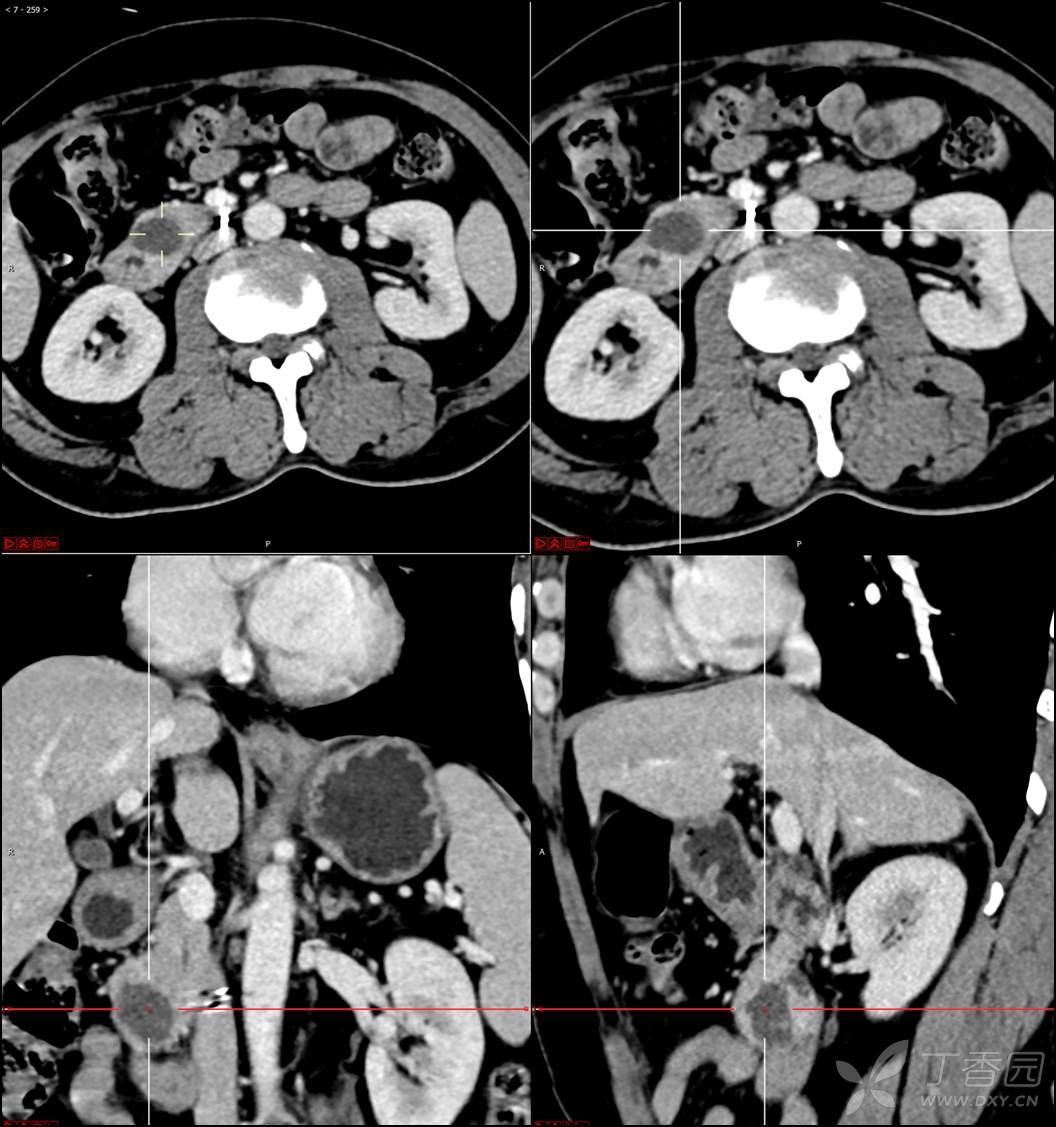

【影诊笔记521】老年男性,黑便就诊,请分析~『回帖即可查阅答案』

患者年龄:67岁

主诉:黑便1周。

现病史:患者1周前无明显诱因出现黑便伴头晕、心慌,无胸闷、胸痛,后仍间断黑便,2022-10-27就诊于某市中医院,行胃镜检查示:十二指肠溃疡伴出血,给予止血、抑酸等对症治疗,效果欠佳。今为行进一步治疗就诊于我院急诊,门诊完善新型冠状病毒核酸检测后以“十二指肠溃疡伴出血”收入我科。患者自发病以来,神志清,精神可,未进食,睡眠可,小便未见异常,黑便,近期体重无明显增减。